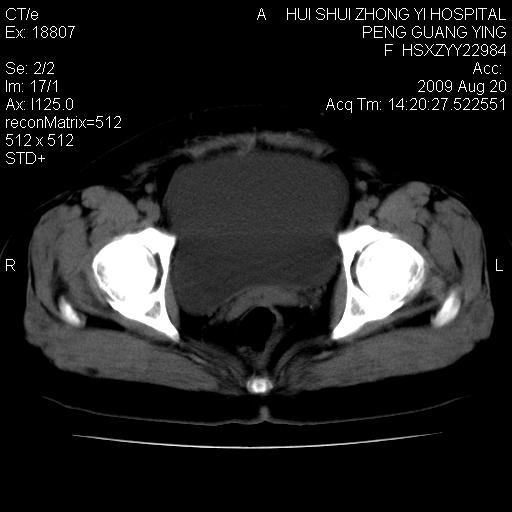

标题: CT21707:女,42岁,因发现下腹部包块2月。 [打印本页]

标题: CT21707:女,42岁,因发现下腹部包块2月。

增强看看,倾向于子宫肌瘤并囊变或腺肌征,宫腔少量积液。

病史不全面,病灶来源可能是子宫或卵巢,若临床有剖腹产、痛经史,则更支持前者,亦更支持子宫腺肌症

目前的影像表现显示肿块位于腹腔及盆腔,但具体定位,分清来源较困难,是否来源于卵巢、子宫无法定论,子宫直肠及子宫膀胱周围脂肪间隙尚较清晰,如果患者有过腹腔好或者盆腔手术史,也可以形成不典型的血中,最好手术后定为定性,我期待结果。